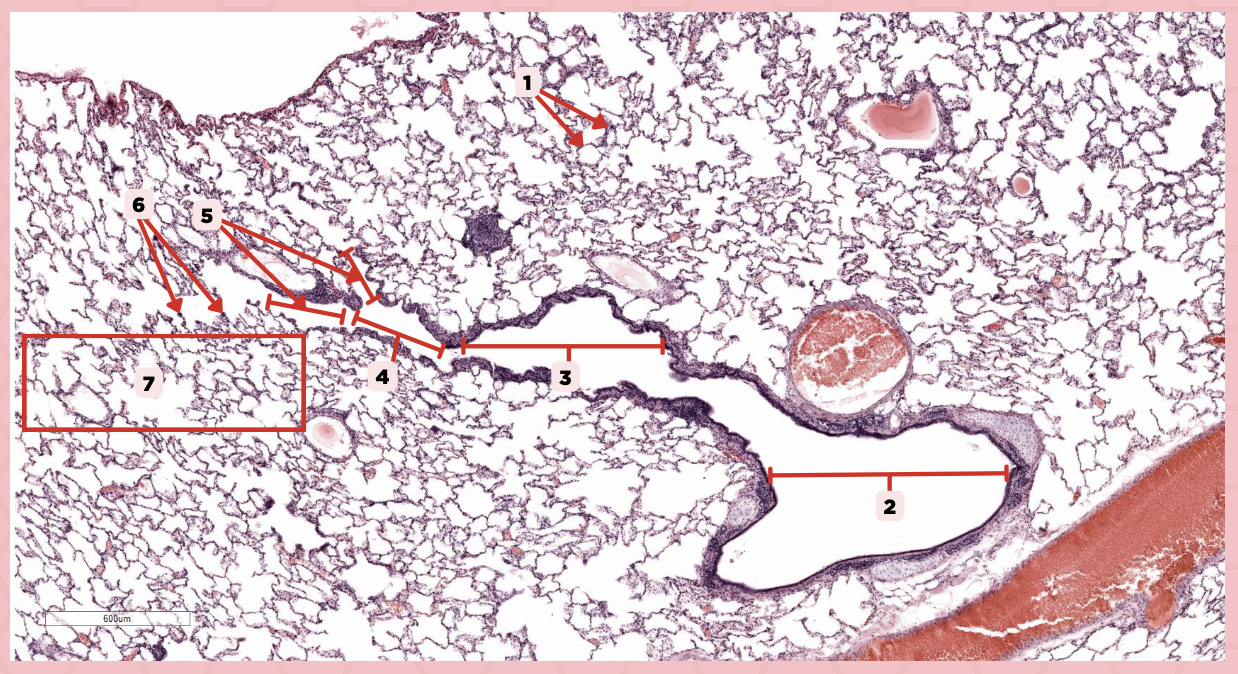

Interalveolar septa

Identify the structure labeled as 1.

Intrapulmonary bronchi

Identify the structure labeled as 2.

Bronchiole

Identify the structure labeled as 3.

Terminal bronchiole

Identify the structure labeled as 4.

Respiratory bronchiole

Identify the structure labeled as 5.

Alveolar ducts

Identify the structure labeled as 6.

Alveolar sacs

Identify the structure labeled as 7.

Bigger and smaller intrapulmonary bronchi

What are the two types of intrapulmonary bronchi?

Pseudostratified epithelium (bigger bronchioles), Simple columnar or cuboidal (smaller)

What are the types of epithelium in No. 3?

Deoxygenated blood

What type of blood does vessel No. 1 carry?

Connective tissue septae

Where would No. 2 be located?

Pulmonary artery

Identify the structure labeled as 1.

Tributary of pulmonary vein

Identify the structure labeled as 2.

Oxygenated blood

What type of blood does this vessel supply?